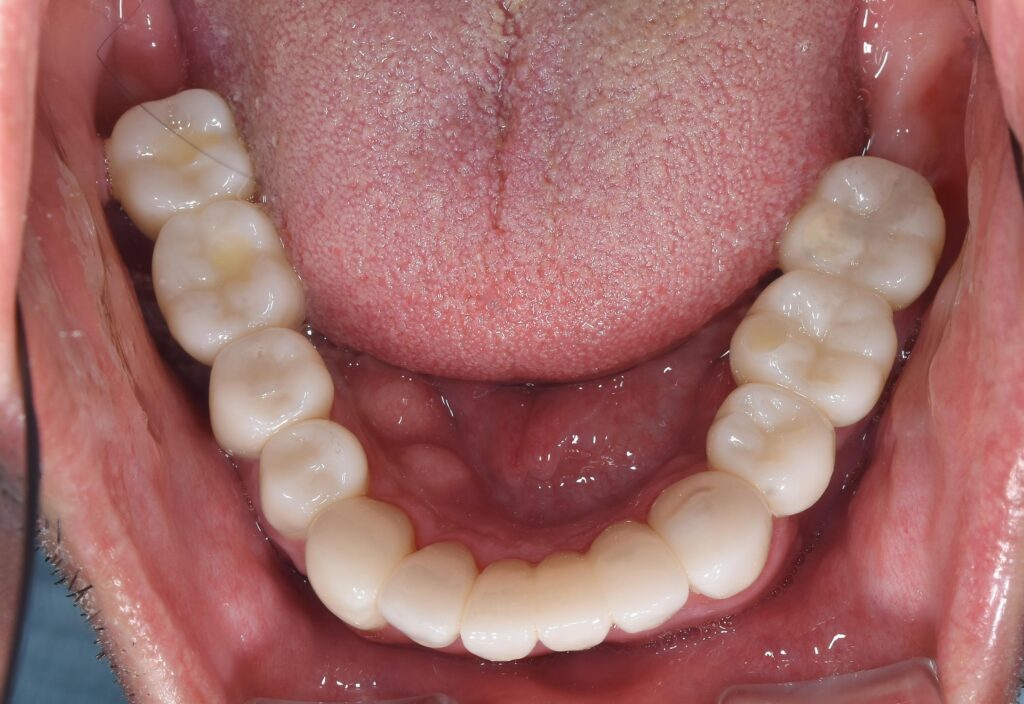

そして、治療を終了した状態が以下のようになります。

【治療終了時】

いかがでしょうか。

患者様には大変満足いただけました(^^♪